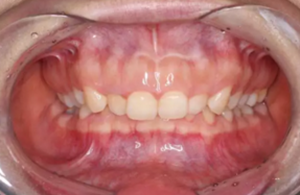

前牙正常覆合

前牙閉鎖合-深覆合

前牙正常覆蓋

前牙閉鎖合覆蓋